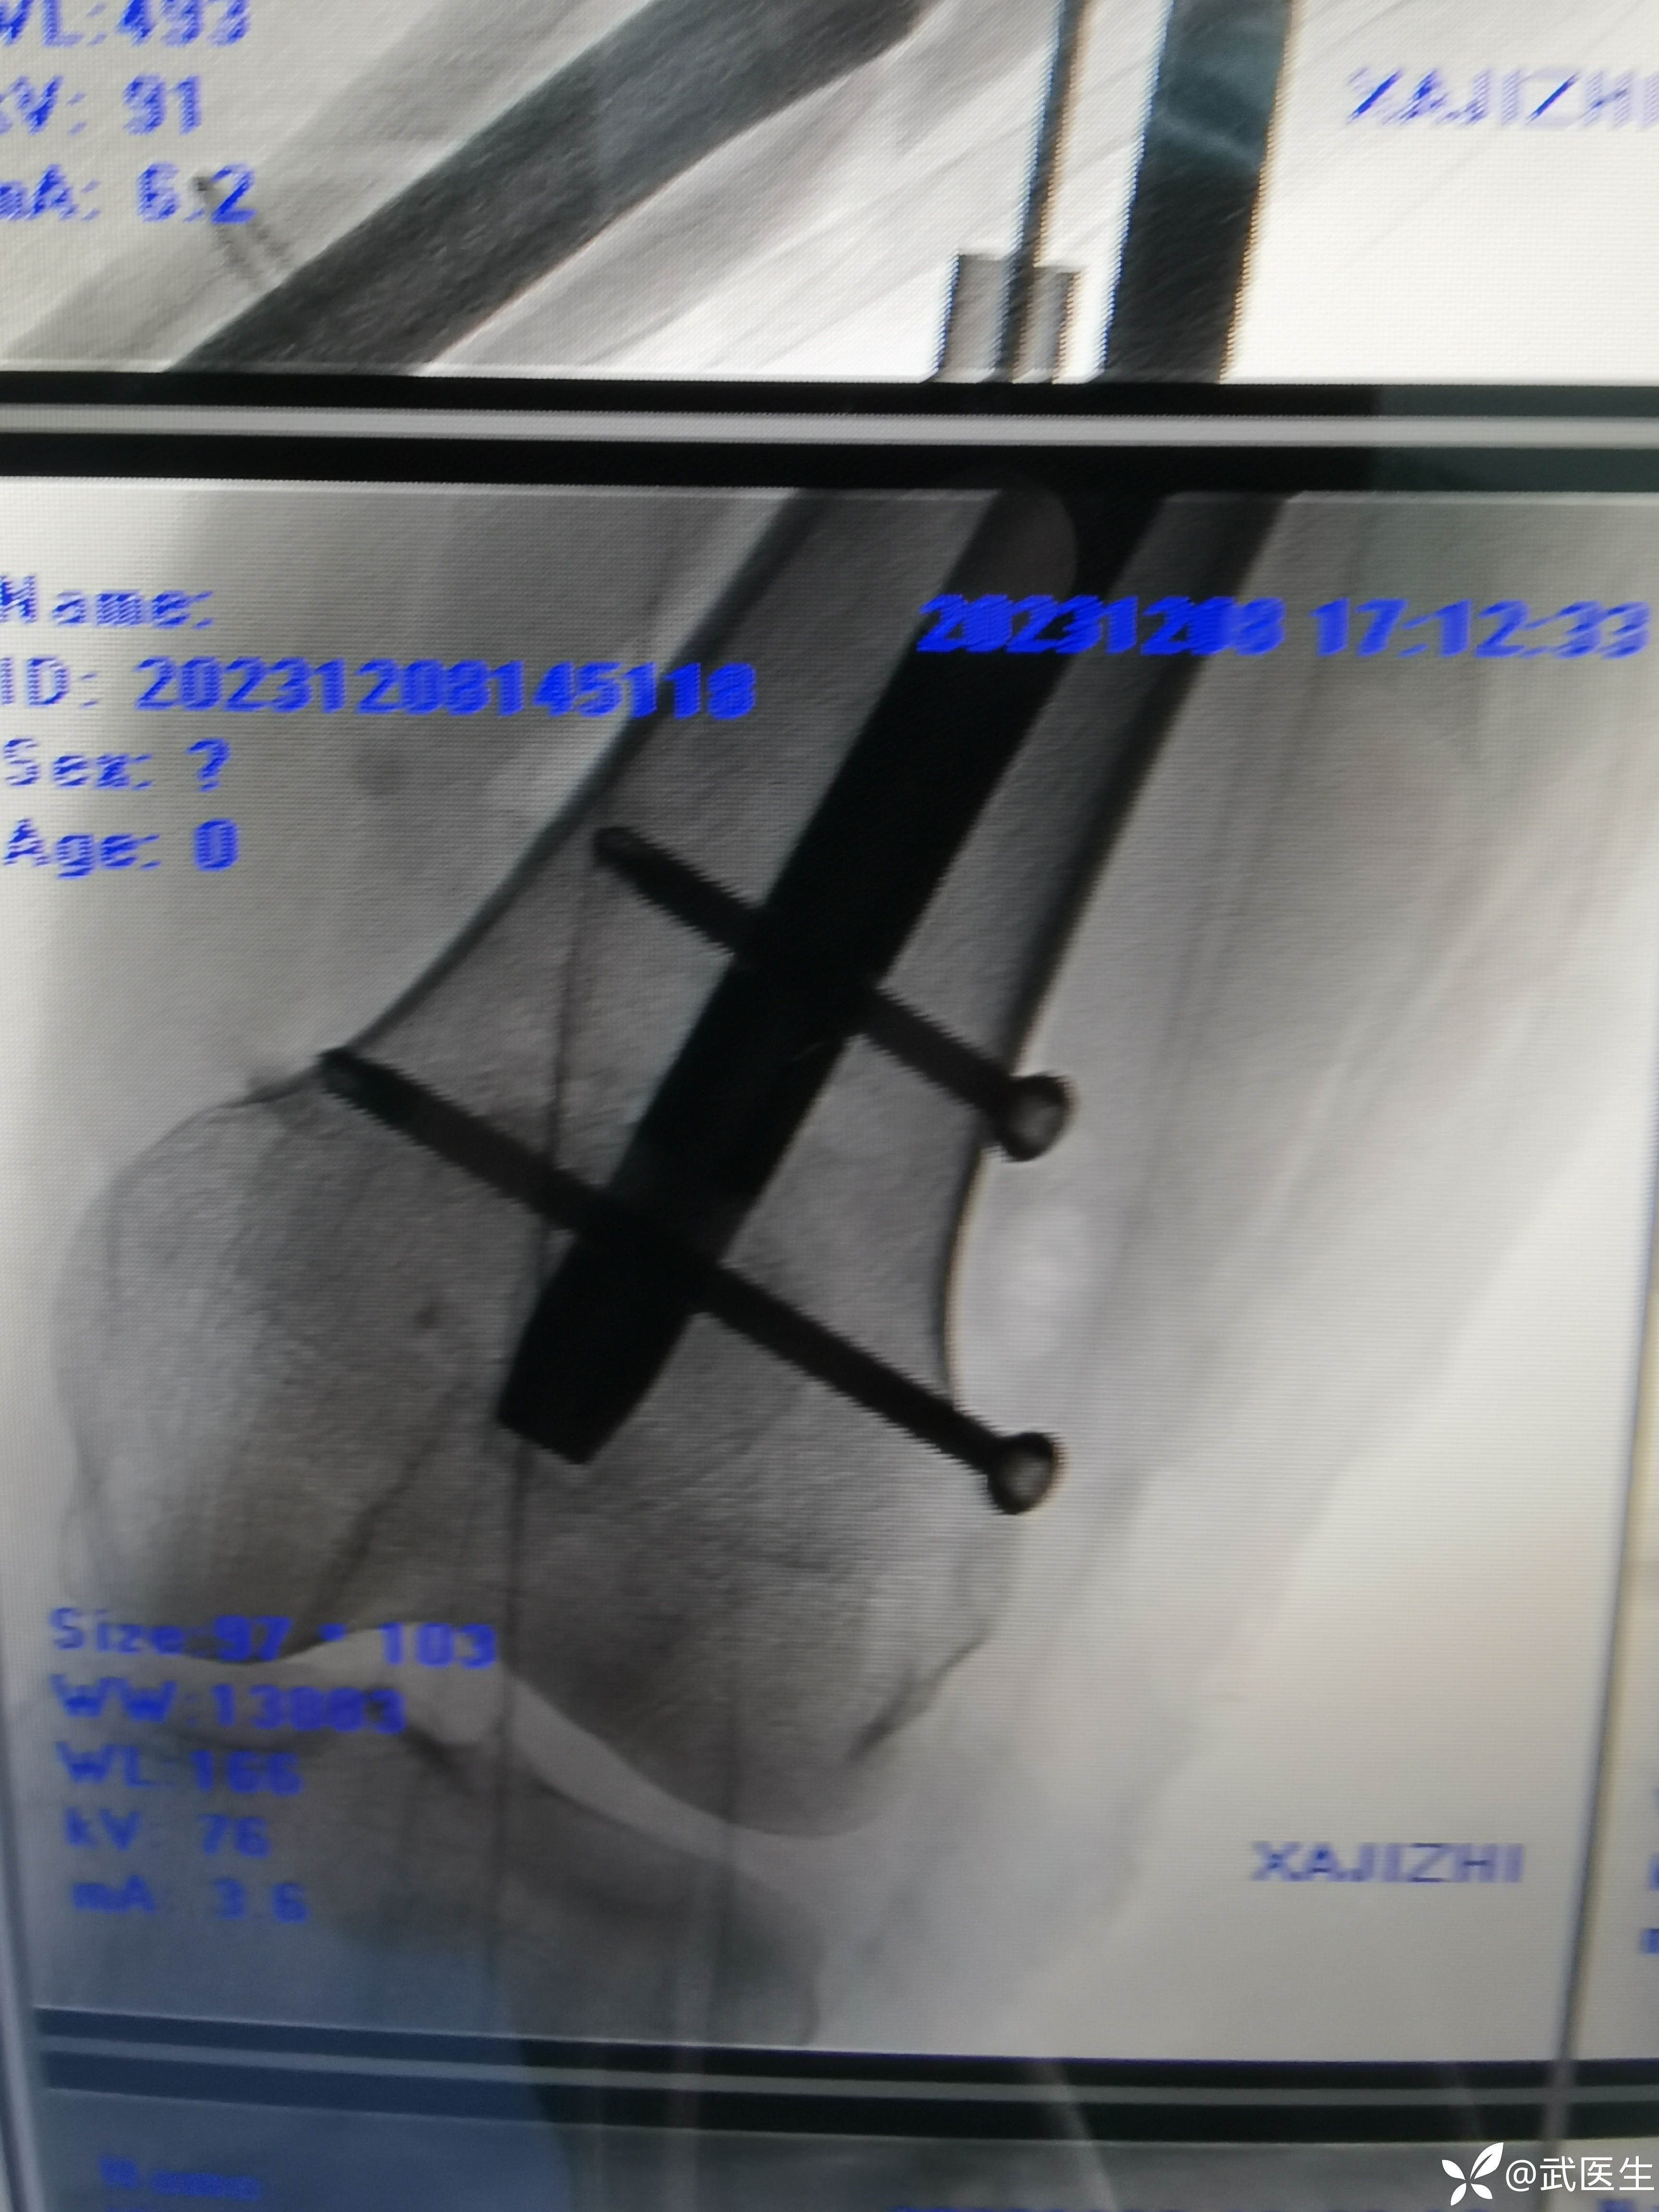

最终如下

还行吧,顶天立地,断端对位良好,头颈钉偏后置入但都在头内固定牢固可靠。